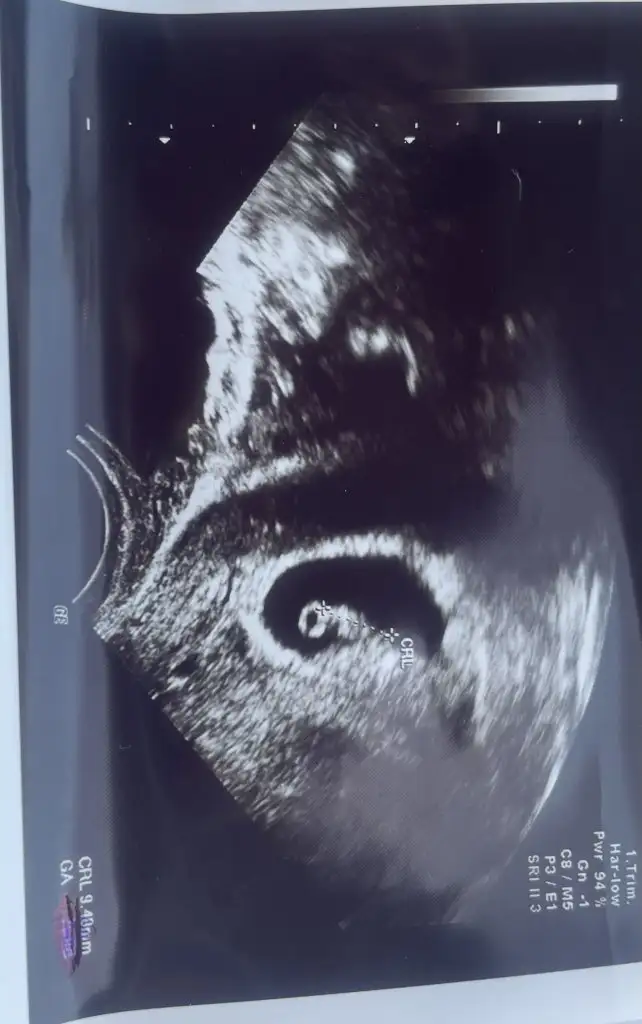

Kuzum tam ortada duruyor ya bilemedim yanlış bir şey söylemek istemiyorum 6 haftalım yok mu